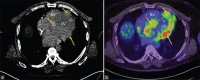

Cardiac Metastasis of Malignant Melanoma